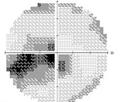

视野的改变也很有特点,常常以中心暗点或哑铃状暗点为主,不像前部缺血性视神经病变,以水平半视野改变为主要表现形式。